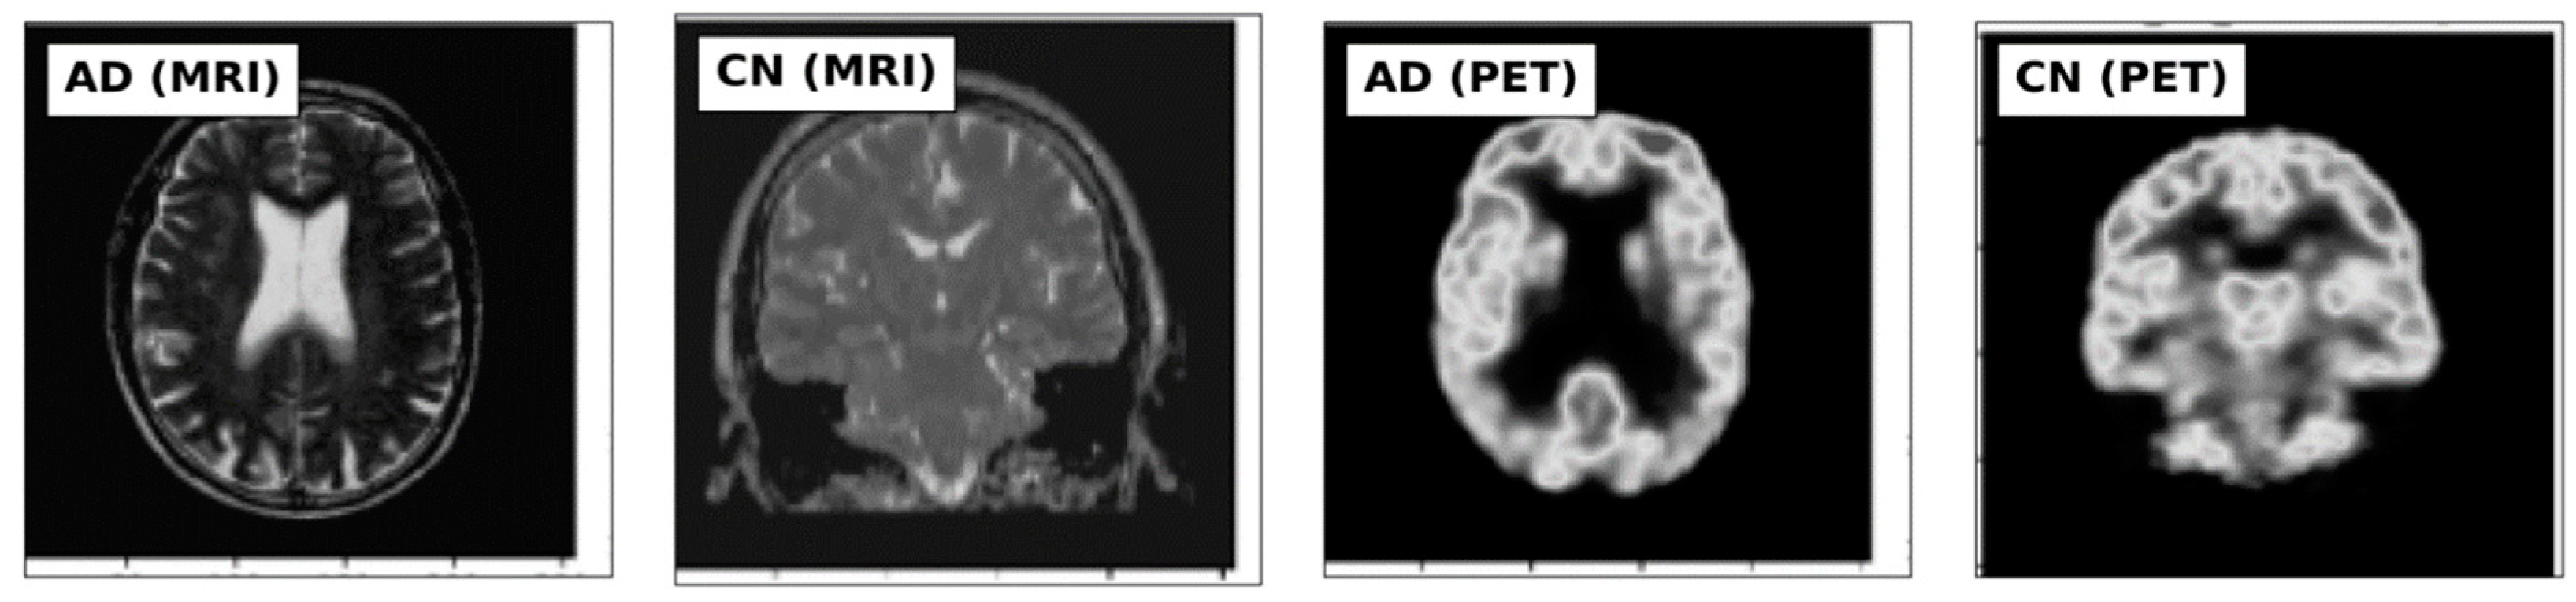

This study utilized MRI and PET images obtained from the official website of Harvard University (http://www.med.harvard.edu/AANLIB/home.html (accessed on 15 September 2023)), the ADNI website (https://adni.loni.usc.edu (accessed on 15 September 2023)), and the OASIS website. The brain images under consideration are categorized into two distinct stages, namely Cognitive Normal (CN) and Alzheimer’s Disease (AD). 50 images of each of the stages are downloaded from each website, making a total of 300 images. PET images are in red, green, and blue (RGB) while MRI images are in black and white. Figure 2, Figure 3 and Figure 4 show sample the datasets used from AANLIB, ADNI, and OASIS database, respectively.

Figure 2.

Sample Images from the AANLIB database.